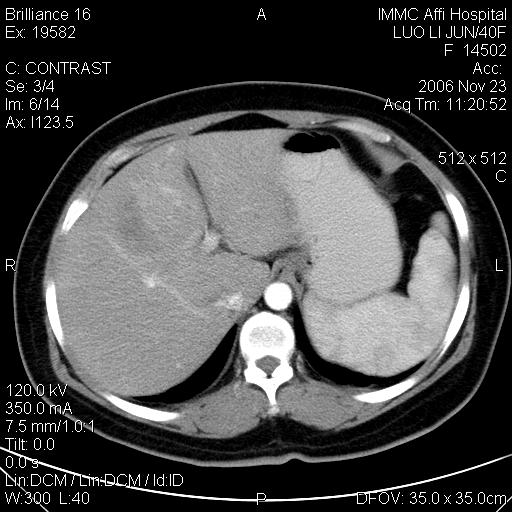

标题: CT5664:我也发一个肝脏的片子大家看看

很典型的肝癌。

速升速降,典型肝癌.

支持-----考虑肝癌----[-从片上看增强早期应该是动脉晚期即门脉早期]

是啊,典型的早出早归!

快进快出典型肝癌.

符合肝癌的增强特征。支持肝癌!

病灶好圆!可能恶性度不高。

不能除外肝细胞腺瘤吧,还是得结合病史。

很好的片子,可惜增强做的比较失败,a期时间没有把我好,实际到了静脉早期了,否则会更典型。

最终考虑是肝腺瘤